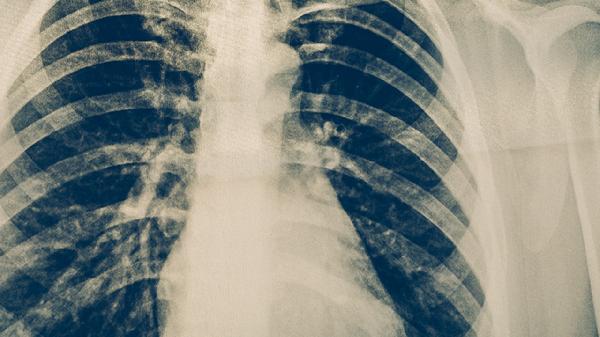

清肺十八味丸中的黄芩、桑白皮等成分具有清热泻火的作用,能缓解因肺热引起的干咳、咽喉肿痛等症状。对于风热感冒早期出现的咳嗽、痰黄黏稠等情况,遵医嘱使用该药可帮助减轻气道炎症反应。